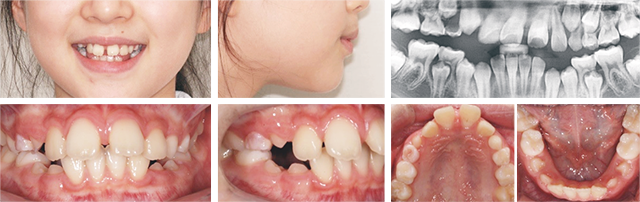

위 앞니가 고르지 않고 돌출되어 치료를 위해 내원한 청소년으로 진단 결과 발치/비발치 경계에 속하는 경우. 부모께서 가급적 이를 빼지 않길 원하셨고 아직 골격 성장이 완료되지 않은 것으로 판단되어 급속 구개 확장 장치(RPE)를 이용하여 발치를 하지 않고 공간을 확보하여 교정 치료를 진행하였습니다.

치료 결과 앞니 돌출이 개선되고 뻐드러짐 없이 가지런하고 잘 물리는 건강한 치열이 만들어짐. 초진에 비해 입도 약간 들어가 자연스러운 입술모양으로 교정이 완료 되었습니다.